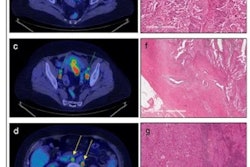

FIGO stage II pathologically confirmed moderately differentiated adenocarcinoma in a 57-year-old female patient. (A) Axial PET/MR images. (B) Axial MR T2-weighted images. (C) Axial PET/CT images. (D) Axial CT images. (E) Sagittal PET/MR images. (F) Sagittal PET/CT images. PET/MRI and MRI show the endometrial carcinoma invading the cervical stroma. PET/CT also shows the endometrial carcinoma invading the cervical stroma, yet the extension of the tumor is difficult to determine. The PET/MRI and PET/CT staging were consistent with the pathological stage, namely FIGO stage II. The white arrow indicates endometrial carcinoma. Image courtesy of BMC Cancer.

FIGO stage II pathologically confirmed moderately differentiated adenocarcinoma in a 57-year-old female patient. (A) Axial PET/MR images. (B) Axial MR T2-weighted images. (C) Axial PET/CT images. (D) Axial CT images. (E) Sagittal PET/MR images. (F) Sagittal PET/CT images. PET/MRI and MRI show the endometrial carcinoma invading the cervical stroma. PET/CT also shows the endometrial carcinoma invading the cervical stroma, yet the extension of the tumor is difficult to determine. The PET/MRI and PET/CT staging were consistent with the pathological stage, namely FIGO stage II. The white arrow indicates endometrial carcinoma. Image courtesy of BMC Cancer.In addition, an analysis of quantitative measures based on F-18 FDG PET/MRI radiotracer uptake by the tumors and nearby tissue were significantly different between stage I and stage III tumors, the authors wrote.